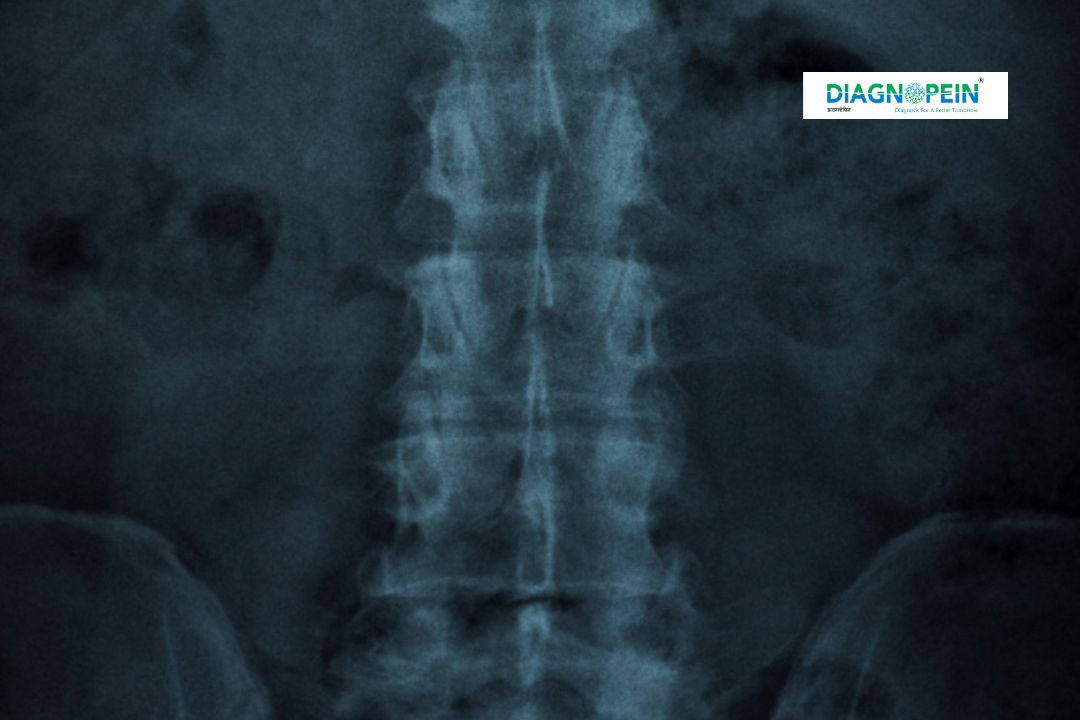

The X-Ray Pelvis with Both Hip Joints is a detailed diagnostic imaging test that captures the pelvic bone and hip joints in a single frame. It helps radiologists and orthopedicians visualize the alignment, bone density, and joint structure to detect injuries, fractures, or bone abnormalities.

The X-Ray Pelvis with Both Hip Joints evaluates several anatomical and diagnostic parameters, including:

1. Pelvic bone shape and symmetry.

2. Acetabulum and femoral head alignment.

3. Joint space narrowing or bone erosion.

4. Fractures, lesions, and calcifications.

5. Hip joint congruency and deformities.